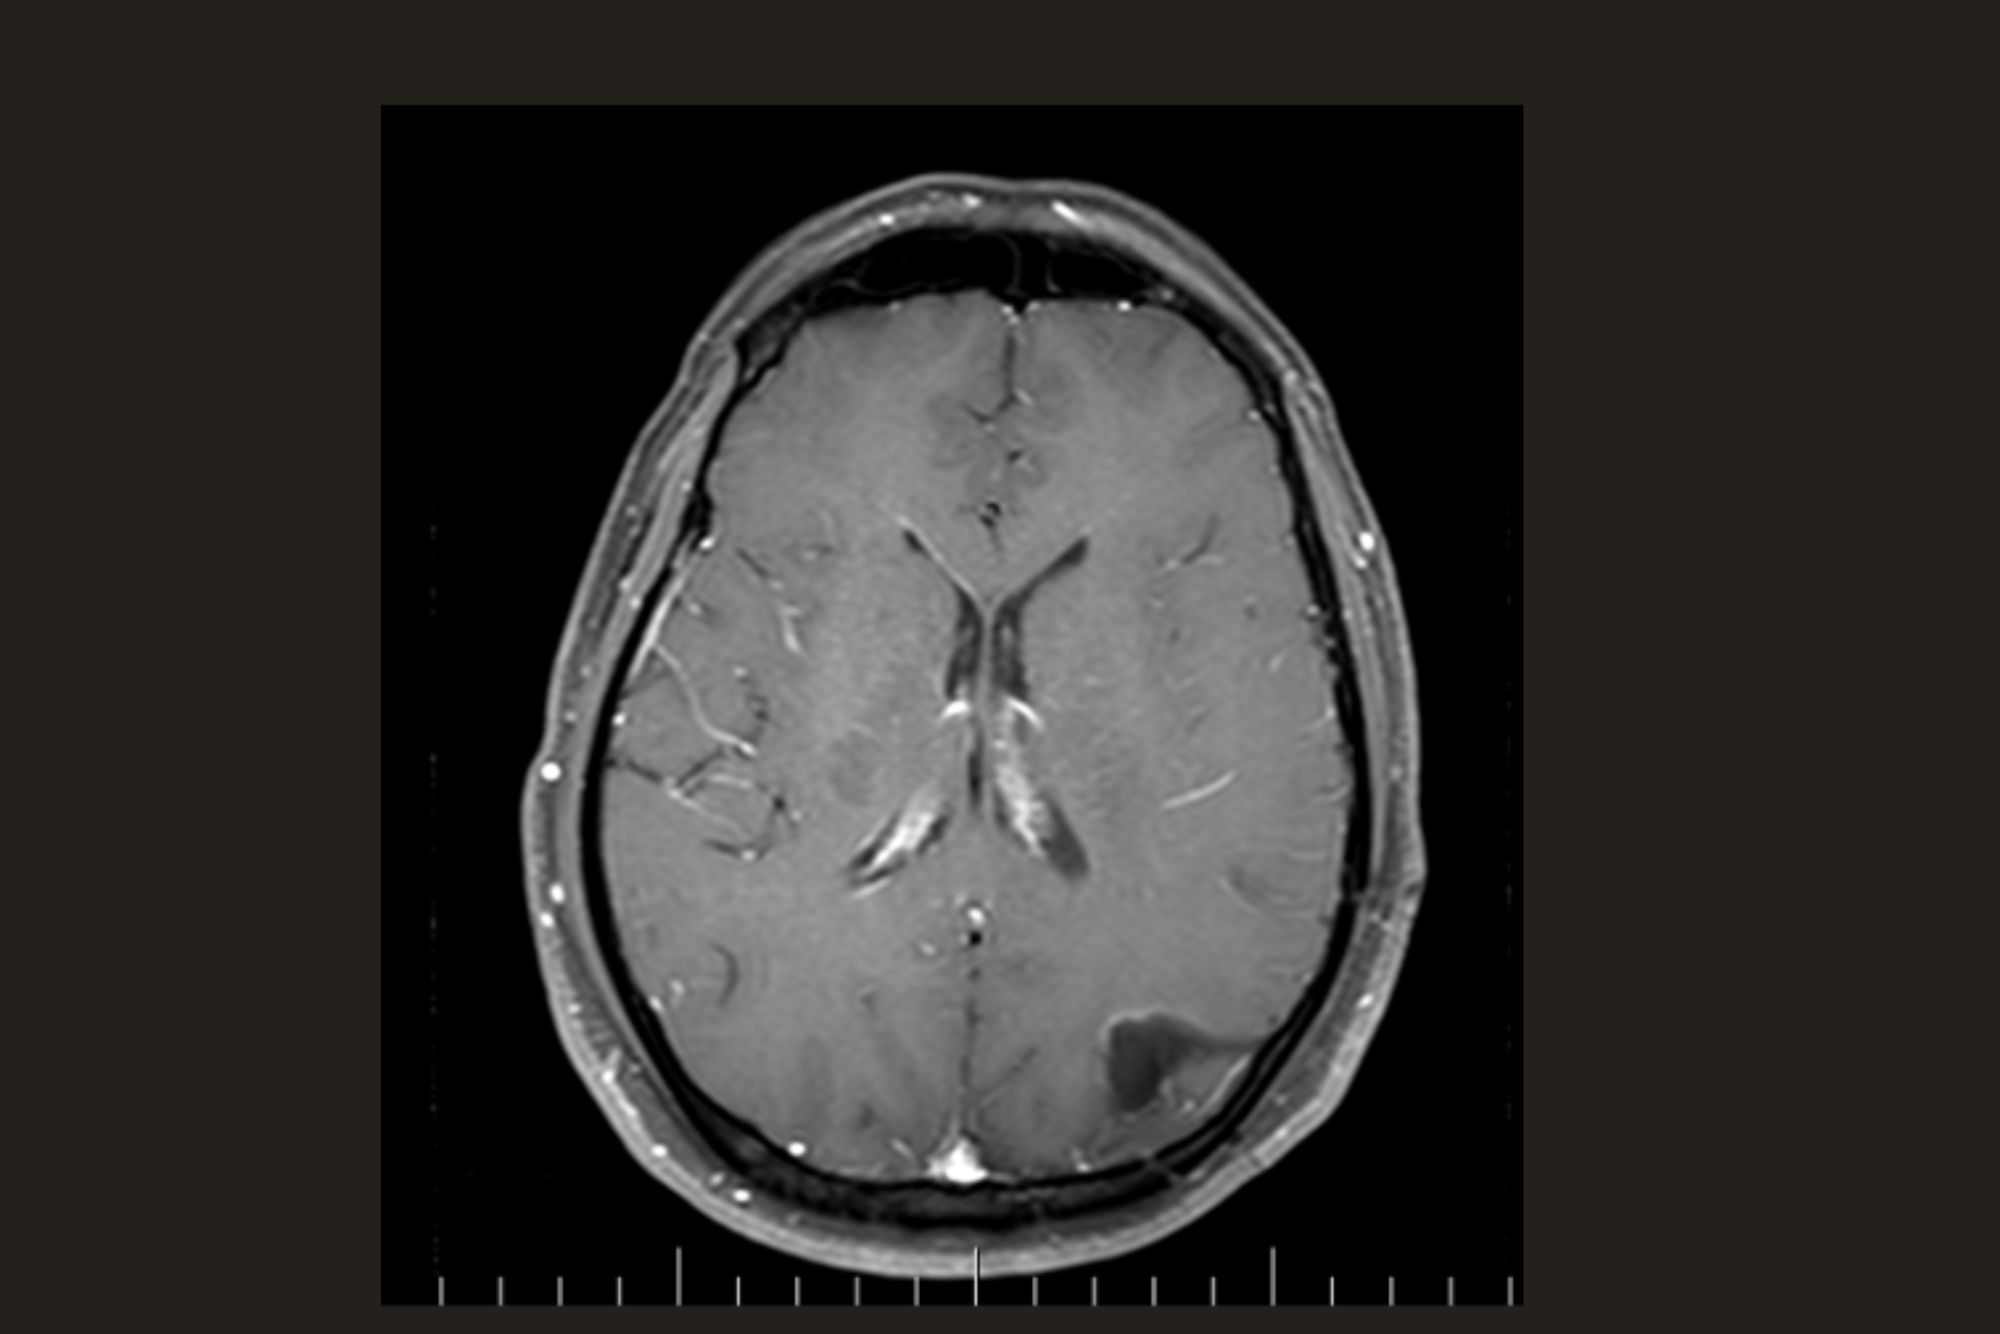

Grade II Glioma

Preoperative MRI

28 yr. Gentleman presenting with single episode of GTCS

No Neurological deficits

1 year Post operative contrast MRI